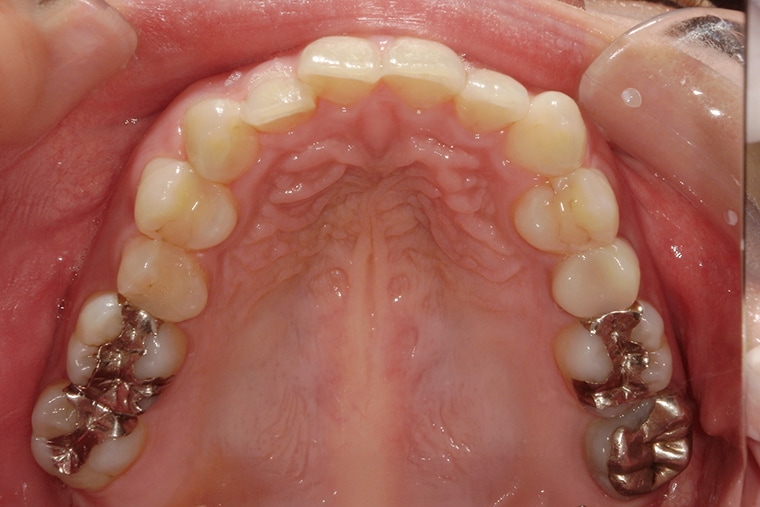

Case Study32歳女性ガタガタな歯のマウスピース矯正-矯正期間6ヶ月(2024年1月開始)